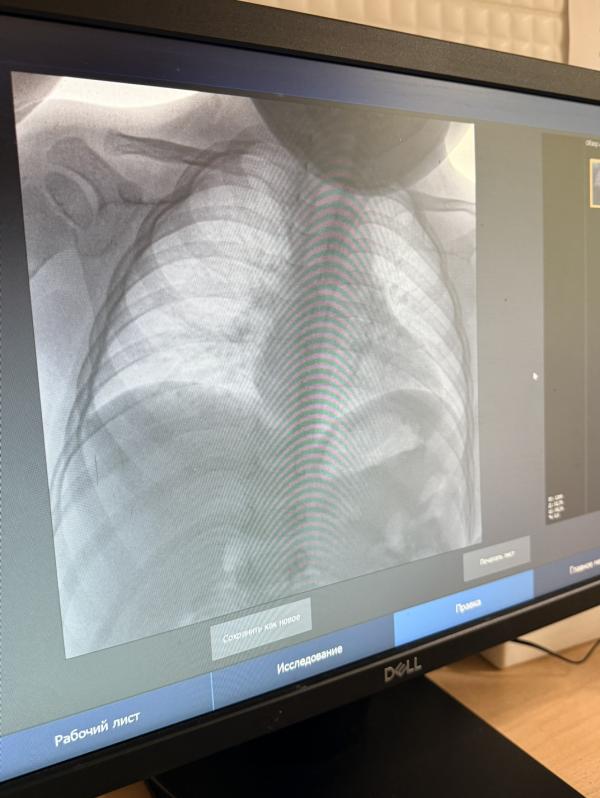

у нас пневмония 😩

да у нас вообще какая-то скрытая пневмония, ребенок как будто здоров, только влажный кашель, я бы даже и не подумала что это пневмония, чудом узнали просто